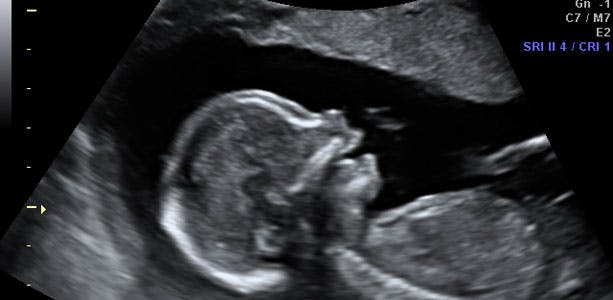

Gravid uge 17: Kolbøtter og saltomortaler

Mængden af fostervand er nu omkring 200 milliliter, og der er masser af plads til at slå kolbøtter og saltomortaler. Ved fødslen kan man ofte se hvide "fedtperler" i fostervandet, som stammer fra dit barns fosterfedt. I slutningen af ugen måler barnet cirka 17 centimeter fra hoved til fod og vejer omkring 260 gram. Hovedet måler cirka 3,8 centimeter i diameter.